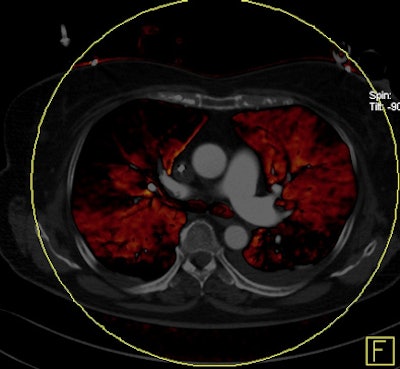

Dual-energy CT enables the selective display of iodine distribution within the pulmonary parenchyma following contrast-enhanced pulmonary CT angiography, which in turn permits the calculation of perfusion defect (PD) size in patients with suspected PE.

Depending on the shape and pattern of the defects at dual-energy CT, perfusion defects due to PE can generally be distinguished from, for example, patchy defects signaling other pathologies of the lung parenchyma, Bauer said.

The researchers measured perfusion defect size in the lung parenchyma caused by PE on dual-energy iodine distribution maps, and expressed it in two ways: as absolute quantification (VolPD in mL) and relative to the total lung volume (RelPD in %).

"When we did lung perfusion, the analysis was restricted to the field-of-view," which is limited due to the smaller second detector on the dual-source CT scanner, he said. As a result "there were 40 patients with no coverage loss, eight patients with up to 5% coverage loss, and five patients with up to about 10% of coverage loss in the peripheral" areas of lung parenchyma, he said.

The 17 patients with right heart strain had significantly higher perfusion volume (215.4 mL versus 73.3 mL, p < 0.01) and relative perfusion defect sizes (9.9% versus 2.9%) compared to patients without right heart strain (perfusion defect sizes for both perfusion defect volume and relative perfusion defect size), Bauer said.

| Patient with bilateral segmental and subsegmental PE and large perfusion defects on dual-energy iodine distribution maps. All images courtesy of Dr. Ralf Bauer. |